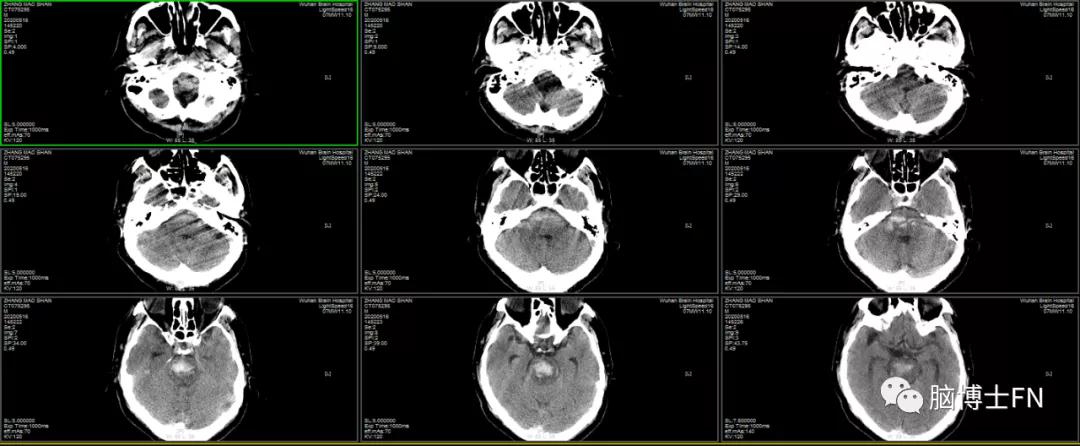

入院头部CT